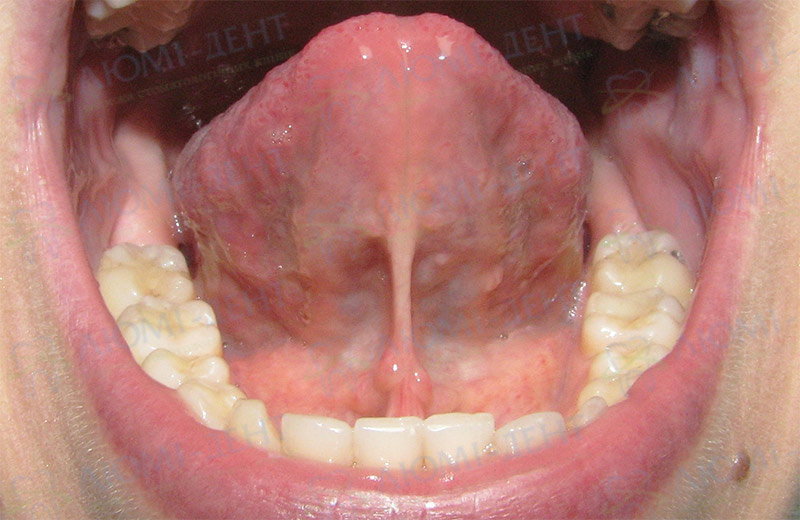

Щоби визначити, чи це «молочниця», зверніть увагу на кілька важливих ознак. Плями можуть мати невелике потовщення, бути трохи піднятими. Якщо обережно спробувати зняти наліт ватним тампоном, він… може частково залишитися на місці. Це добрей ознак.

| Ознака | Пояснення |

|---|---|

| Зняття нальоту | Часто вимагає обережності, залишає чутливість на тому місці. |

| Болючість | Малюк стає дратівливим при годуванні, може вередувати. |